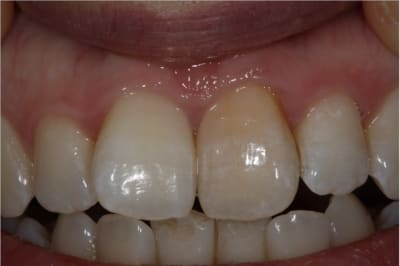

Cas simple et pourtant ... j'ai été obligé de prendre un risque . Lequel ?

PS/ Je prolonge le ttt jusqu'à la semaine prochaine en espérant gagner encore un poil sur l'opacité .

C'est un blanchiment unitaire sur dent vivante ayant eu traumatisme.

C'est un blanchiment interne comme si l'endo était faite (après recherche effrénée d'un hypothétique canal), et après contrôle +++ d'une isolation +++ . La patiente n'a aucun souvenir d'un traumatisme sur cette dent .